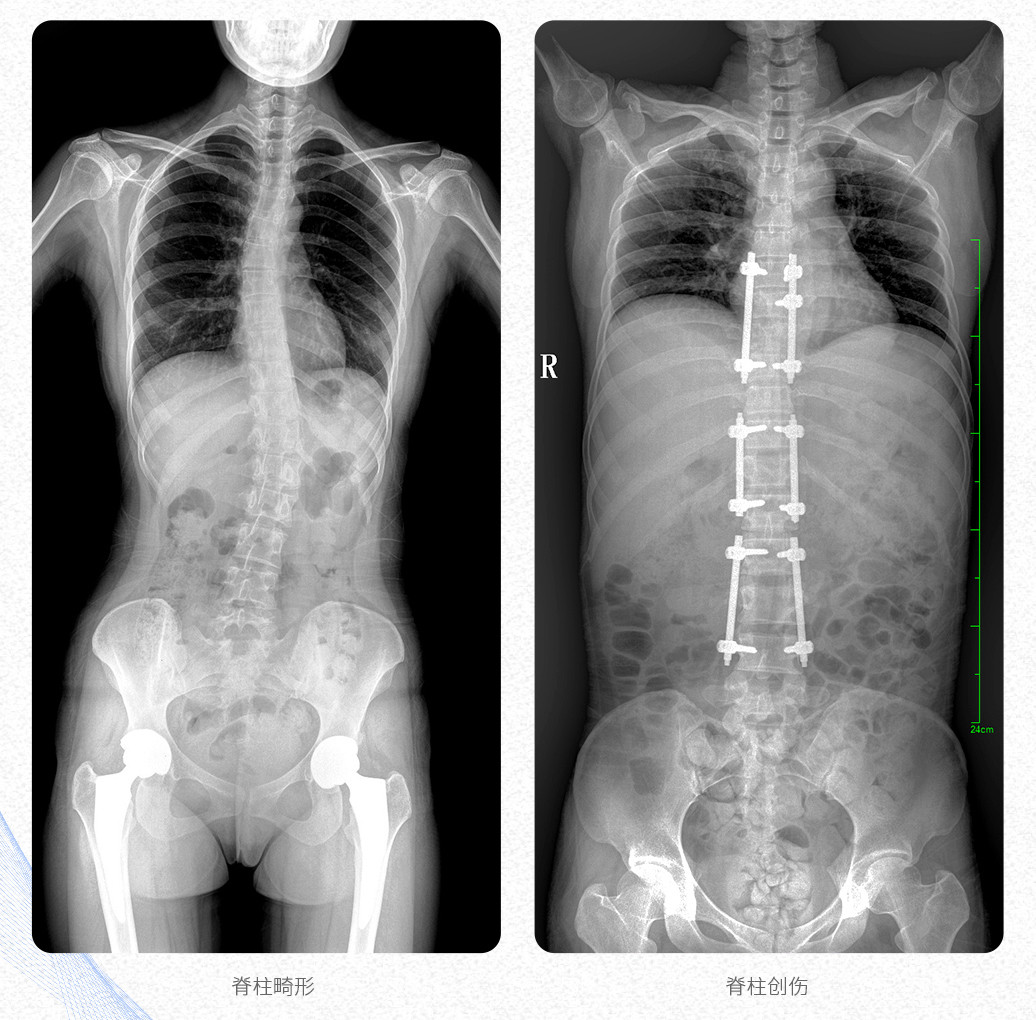

这款大视野U形臂DR的PLX8600数字化医用X射线摄影系统主要应用于骨科、创伤科、脊柱正畸科、放射介入科等科室;可供各级医院支持全脊柱摄影、双下肢摄影、脊髓造影、复杂创伤、人工关节置换、关节损伤的修复重建等大视野临床应用。

这款PLX8600数字化DR采用17"*34"有效视野,一次成像不拼接。相较于多张摄影再软件拼接的DR设备,PLX8600动态平板DR解决了拼接图像存在密度不均匀,拼接处图像配准和放大效应等问题,给临床带来了真正的大视野影像解决方案,高清画质,准确成像不失真,可一次性覆盖全脊柱或双下肢影像。

【产品临床图片】